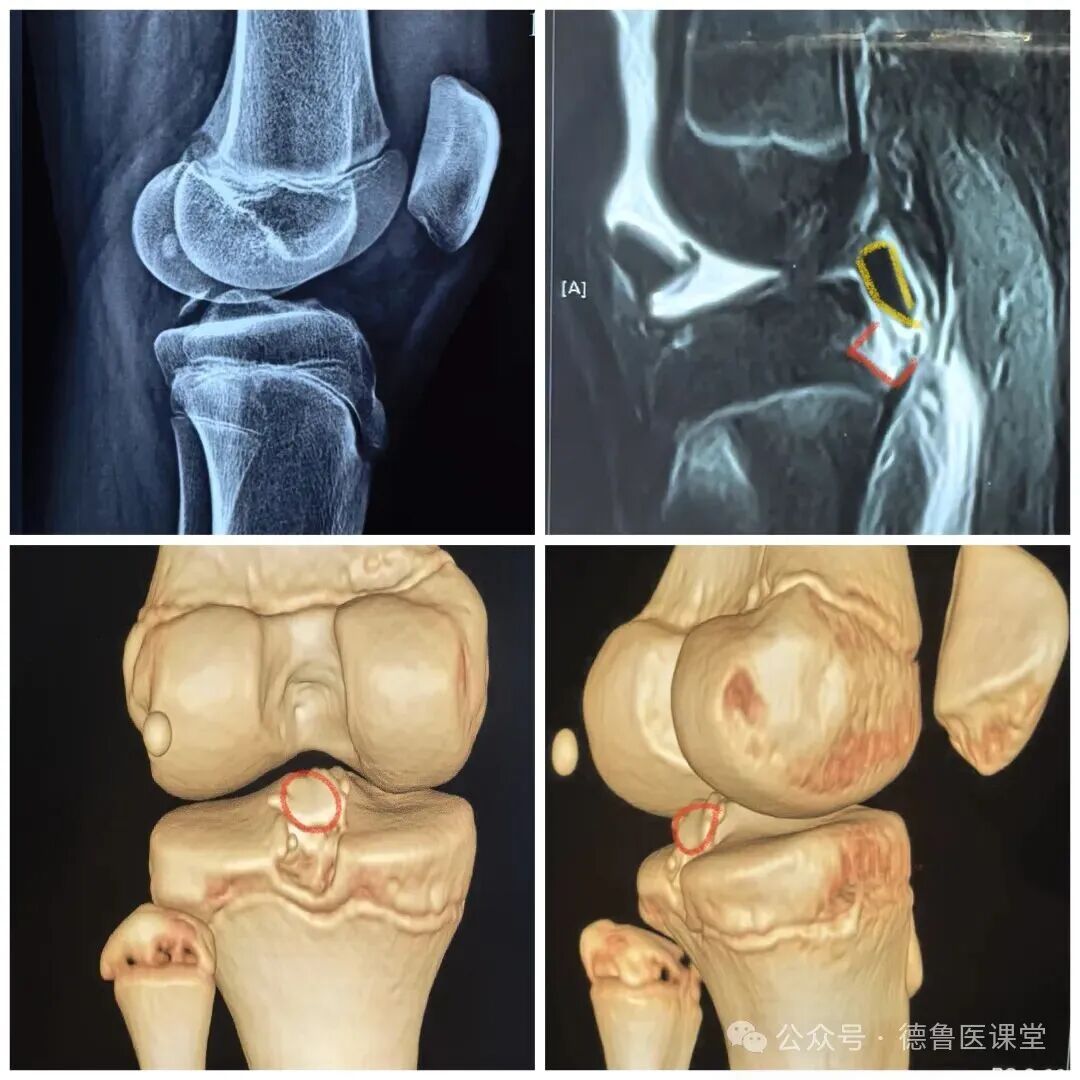

后叉止点撕脱骨折

Ⅲ型 完全移位

查体不稳